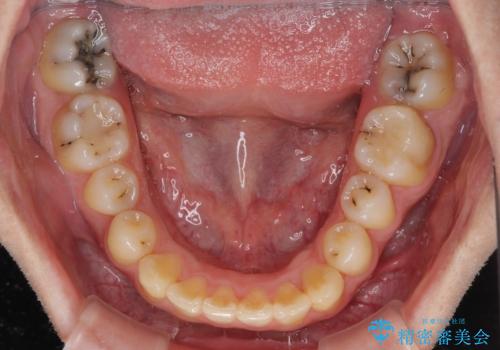

- 前歯のクロスバイトと、大学生のころから放置している虫歯を気にして来院された患者様です。

マウスピースでの矯正治療を希望されていましたが、前歯のクロスバイトは不十分な仕上がりや歯髄壊死などのリスクが高くなるため、術前にワイヤーで大まかに整えてからインビザラインにて矯正治療を行うこととしました。

奥歯の虫歯は抜歯が必要であったので、矯正治療前に抜歯をし、矯正治療と並行してインプラントによる補綴治療を行うこととしました。